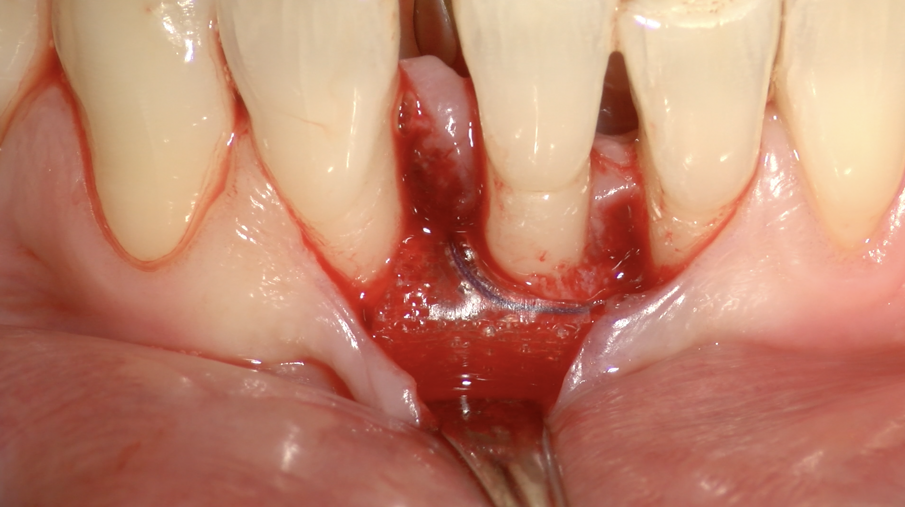

Il Paziente veniva premedicato con Zitromax 500 mg e Ibuprofene 400 mg. Eseguita anestesia loco regionale con articaina 1:100.000 con adrenalina veniva sollevato un lembo muco periosteo a spessore totale con tecnica di preservazione di papilla MPPT (Cortellin i 1995) e incisione intrasulculare (Figg 6d, 6e). Il difetto in sede interprossimale e vestibolare è stato degranulato con ultrasuoni e curette manuale. Raggiunta la perfetta decontaminazione del sito è stata preparata la barriera GUIDOR matrix barrier partendo dalla configurazione specifica per difetti interprossimali (DC double curved) in modo da renderne corretta la dimensione mesio distale e apico coronale (Fig. 6f) .

Fig. 6d - Lembo sollevato con preservazione papille.

Fig. 6e - Difetto infraosseo mesiale.